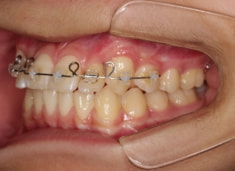

治療前

治療開始時